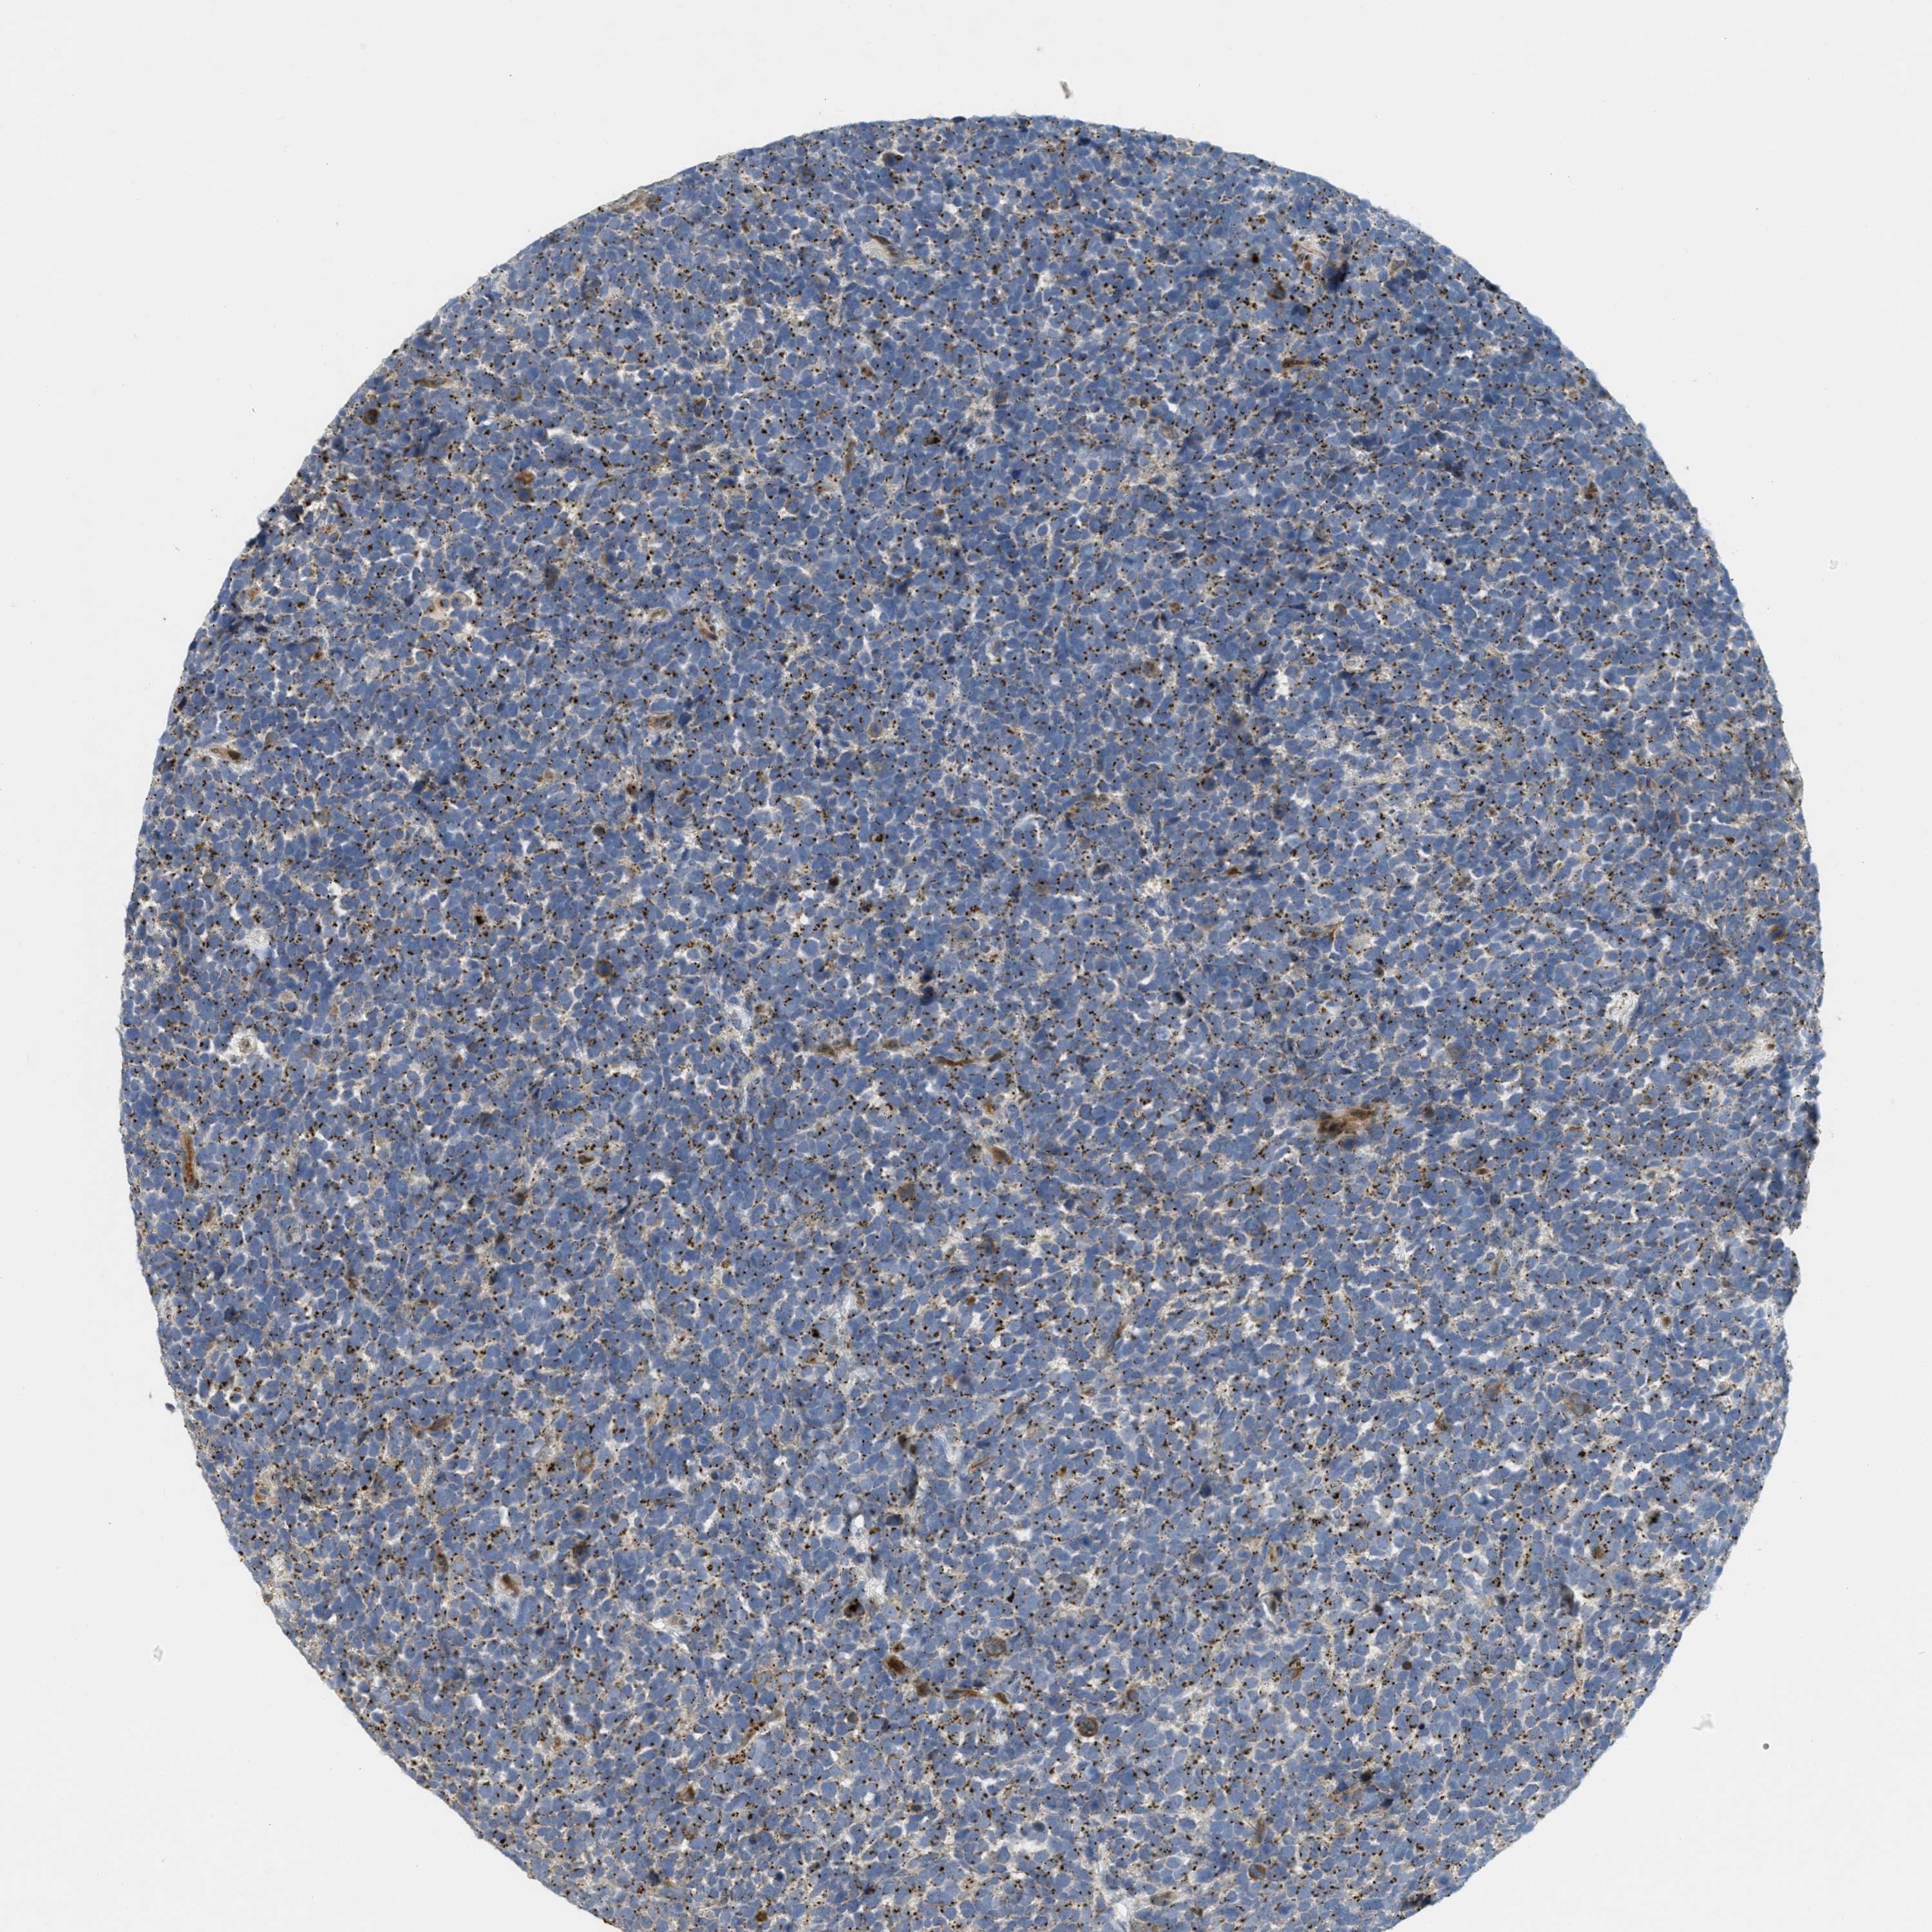

UROTHELIAL CANCER - Protein expressioni

A mouse-over function shows sample information and annotation data. Click on an image to view it in a full screen mode. Samples can be filtered based on level of antibody staining by selecting one or several of the following categories: high, medium, low and not detected. The assay and annotation is described here.

Note that samples used for immunohistochemistry by the Human Protein Atlas do not correspond to samples in the TCGA dataset.

Antibody stainingi

Antibody staining in the annotated cell types in the current human tissue is reported as not detected, low, medium, or high, based on conventional immunohistochemistry profiling in selected tissues. This score is based on the combination of the staining intensity and fraction of stained cells.

Each image is clickable and will lead to virtual microscopy that enables deeper exploration of all samples and also displays staining intensity scores, fraction scores and subcellular localization as well as patient and tissue information for each sample.

Antibody HPA014909

Antibody HPA017347

Urothelial carcinoma, Low grade

Urothelial carcinoma, High grade